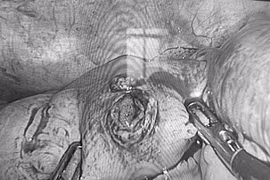

Phẫu thuật cấp cứu giữa đêm bảo toàn buồng trứng cho thiếu nữ đau bụng

Phụ nữ, đặc biệt là trẻ vị thành niên nên khám phụ khoa định kỳ khi có dấu hiệu bất thường như đau bụng kéo dài, bụng to bất thường, rối loạn kinh nguyệt.